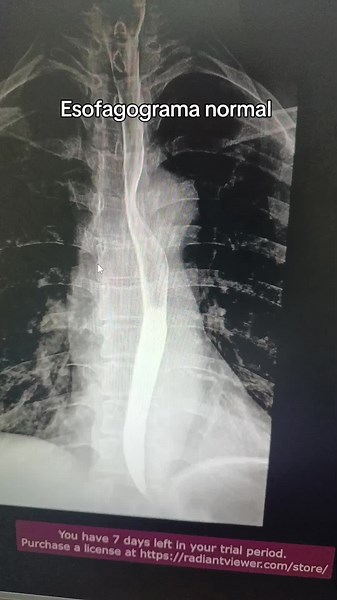

Esofagograma Normal: Importancia en Radiología

已浏览 4.3万 次

9 个月之前

TikTok

gretha.radiologo

Esófagograma

已浏览 2.6万 次

2017年2月13日

YouTube

Radiologia HCG

Normal Esophagram

已浏览 5833 次

2016年5月25日

Nelly Tan